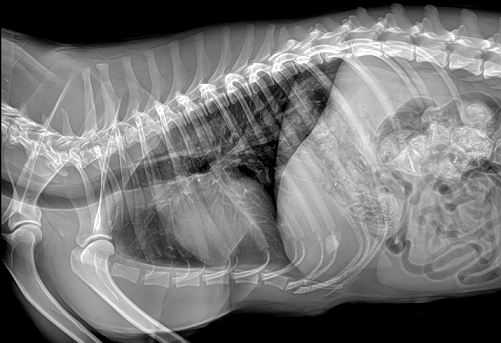

國產(chǎn)品牌普愛醫(yī)療寵物dr采用非晶硅平板探測器,可以令動物影像成像清晰而快速,基本上5s左右就能使動物影像清楚成像且無拖尾現(xiàn)象,而且分辨率高,極限空間分辨率可達(dá)到5.0Lp/mm;

普愛醫(yī)療寵物dr拍攝的高清照片

同時,寵物影像成像尺寸較大,成像尺寸可達(dá)43cm x 43cm,并且以DICOM格式儲存數(shù)據(jù),極大的方便了醫(yī)療工作者們追蹤檢查時使用。同時還支持窗寬、窗位、放大、旋轉(zhuǎn)、正像和負(fù)像轉(zhuǎn)換等顯示功能。如果您想購買普愛醫(yī)療寵物dr,或了解具體技術(shù)參數(shù),歡迎聯(lián)系我們。